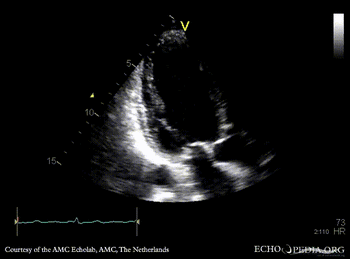

Case 95

Apical and anteroseptal infarction

A4CH: dilated left ventricle, poor function, akinesia of the apex and all midsegments A2CH